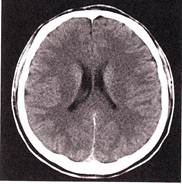

1. Определите метод лучевой диагностики и плоскость исследования.

2. На предыдущих снимках определите анатомическую область применения метода лучевой диагностики.